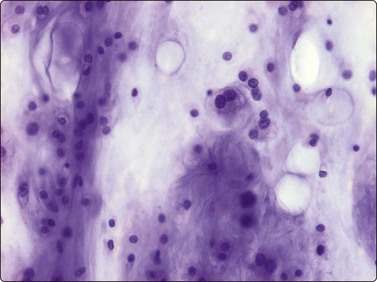

The Langerhans cell histiocytes express S-100 protein and CD1-antigen (Fig. 16.11). According to the Histiocyte Society the definitive diagnosis of Langerhans cell histiocytosis is based on the demonstration of Birbeck granules by electron microscopy or positivity for CD1 antigen.15 The examination of conventionally stained material gives a presumptive diagnosis. The cytological features of Langerhans cell histiocytosis has been recorded in several series.16-18

image image

Fig. 16.11 Langerhans cell histiocytosis (eosinophilic granuloma)

The Langerhans cell histiocytes express (A) S-100 protein and (B) CD1-antigen (Cell block, immunoperoxidase).